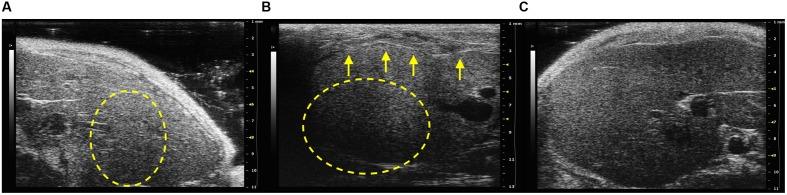

is a gram-negative facultative intracellular bacterium and is the causative agent of cat-scratch disease. Our previous data have established that colonization is able to prevent damages through the polysaccharide A (PSA) in an experimental murine model. In order to determine whether the PSA is essential for the protection against pathogenic effects of in immunocompromised hosts, SCID mice were co-infected with wild type or its mutant ΔPSA and the effects of infection on murine tissues have been observed by High-Frequency Ultrasound (HFUS), histopathological examination, and Transmission Electron Microscopy (TEM). For the first time, echostructure, hepatic lobes length, vascular alterations, and indirect signs of hepatic dysfunctions, routinely used as signs of disease in humans, have been analyzed in an immunocompromised murine model. Our findings showed echostructural alterations in all infected mice compared with the Phosphate Buffer Solution (PBS) control group; further, those infected with and co-infected with ΔPSA presented the major echostructural alterations. Half of the mice infected with and all those co-infected with ΔPSA have showed an altered hepatic echogenicity compared with the renal cortex. The echogenicity score of co-infected mice with ΔPSA differed significantly compared with the PBS control group (p < 0.05). Moreover the inflammation score of the histopathological evaluation was fairly concordant with ultrasound findings. Ultrastructural analysis performed by TEM revealed no significant alterations in liver samples of SCID mice infected with wild type while those infected with ΔPSA showed the presence of collagen around the main vessels compared with the PBS control group. The liver samples of mice infected with showed macro-areas rich in collagen, stellate cells, and histiocytic cells. Interestingly, our data demonstrated that immunocompromised SCID mice infected with and co-infected with ΔPSA showed the most severe morpho-structural liver damage. In addition, these results suggests that the HFUS together with histopathological evaluation could be considered good imaging approach to evaluate hepatic alterations.

是一种革兰氏阴性兼性细胞内细菌,是猫抓病的病原体。我们之前的数据表明,在实验性小鼠模型中,该菌的定殖能够通过多糖A(PSA)预防损伤。为了确定PSA对于免疫功能低下宿主抵御该菌致病作用是否至关重要,将SCID小鼠与野生型或其突变体ΔPSA共同感染,并通过高频超声(HFUS)、组织病理学检查和透射电子显微镜(TEM)观察感染对小鼠组织的影响。首次在免疫功能低下的小鼠模型中分析了回声结构、肝叶长度、血管改变以及肝功能障碍的间接征象,这些征象在人类中通常用作疾病的标志。我们的研究结果显示,与磷酸盐缓冲溶液(PBS)对照组相比,所有感染小鼠均出现回声结构改变;此外,感染该菌和与ΔPSA共同感染的小鼠出现了主要的回声结构改变。与肾皮质相比,感染该菌的小鼠中有一半以及所有与ΔPSA共同感染的小鼠均表现出肝脏回声改变。与PBS对照组相比,与ΔPSA共同感染的小鼠的回声评分有显著差异(p < 0.05)。此外,组织病理学评估的炎症评分与超声检查结果相当一致。通过TEM进行的超微结构分析显示,感染野生型该菌的SCID小鼠肝脏样本无明显改变,而与PBS对照组相比,感染ΔPSA的小鼠主血管周围出现了胶原蛋白。感染该菌的小鼠肝脏样本显示有富含胶原蛋白、星状细胞和组织细胞的大区域。有趣的是,我们的数据表明,感染该菌并与ΔPSA共同感染的免疫功能低下的SCID小鼠表现出最严重的肝脏形态结构损伤。此外,这些结果表明,HFUS与组织病理学评估一起可被视为评估肝脏改变的良好影像学方法。